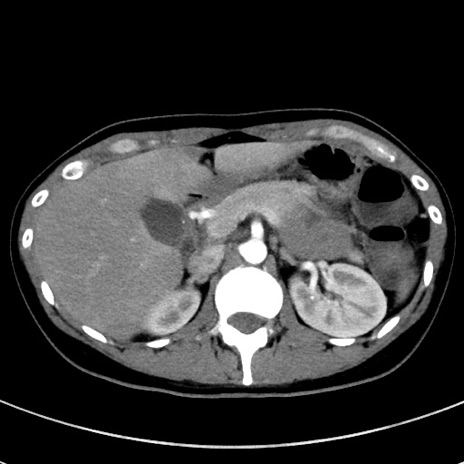

症例17(横断像)

【症例】20歳代女性

【主訴】嘔吐、下腹部痛

【現病歴】昨日夕食後に嘔吐し下腹部痛が出現。本日になっても嘔吐持続し改善しないため来院。

【身体所見】意識清明、BT 37.2℃、BP 108/67mmHg、腹部:平坦、やや硬、下腹部正中から右にかけて圧痛あり、反跳痛軽度あり、tapping pain(+)。

【データ】WBC 13600、CRP 14.94